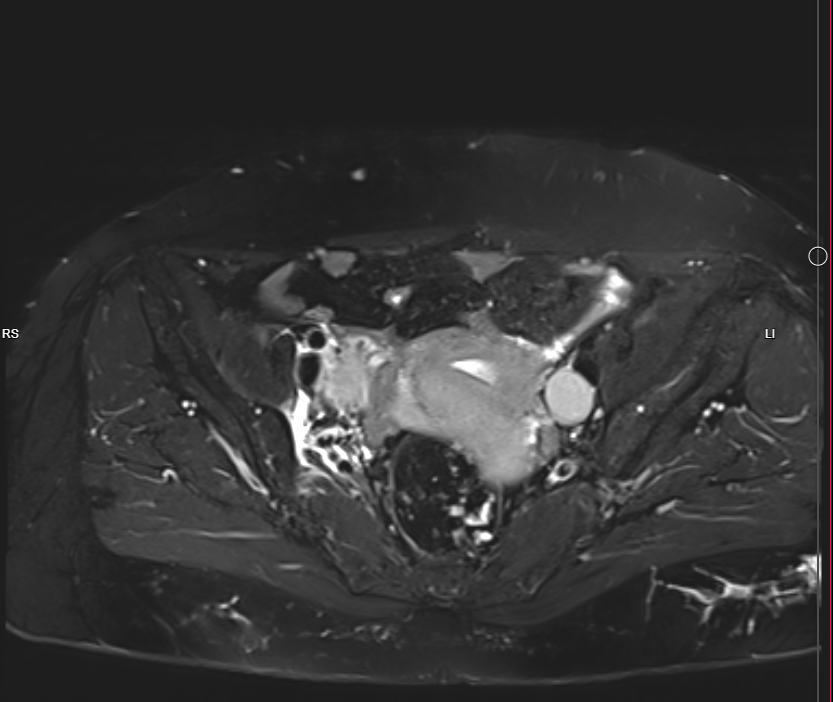

Pelvic MRI With IV Gd:

- Evidence of 7.5 X 4cm mass involves Rt side of uterus reaches endometrium, involves whole thickness of uterus and extends to Rt adnexa, also infiltration of peritoneal reflesion in Rt side of rectouterine pouch, shows marked DWI restriction, picture is suggestive of malignant tumor ?lymphoma ?sarcoma

- Single Lt internal iliac pathological LN, 18mm in short axis diameter, its signal is like uterine mass.

- There is also 26 X 22mm lesion in Rt internal iliac region, but heterogeneous signal ?pathological LN with necrosis

- Mild pelvic free fluid.